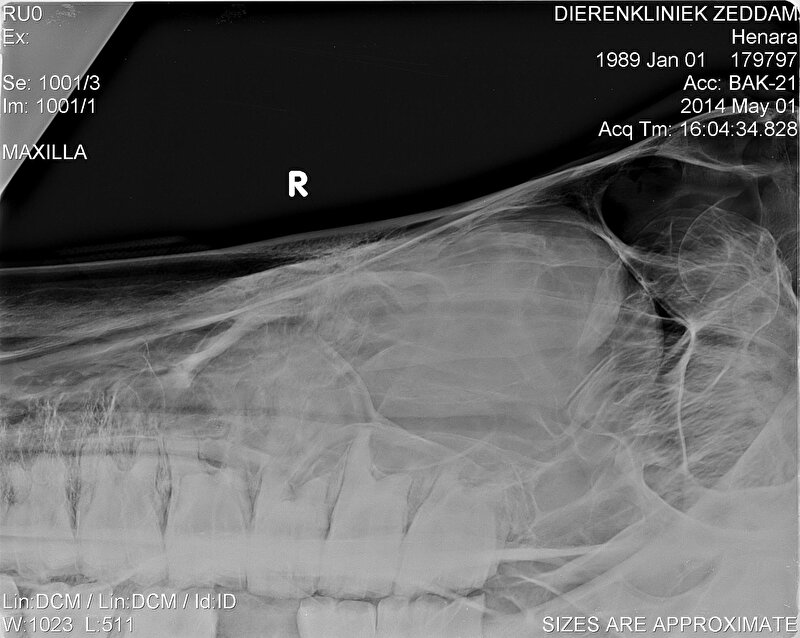

er zijn bij Hannes ondertussen al 5 1/2 kies getrokken, kan gewoon zonder verdoving. Een paard heeft niet hetzelfde gevoel als ons in de kiezen. Leuk vond ze het niet maar als je niet meer kan eten door een losse kies moet je wat...